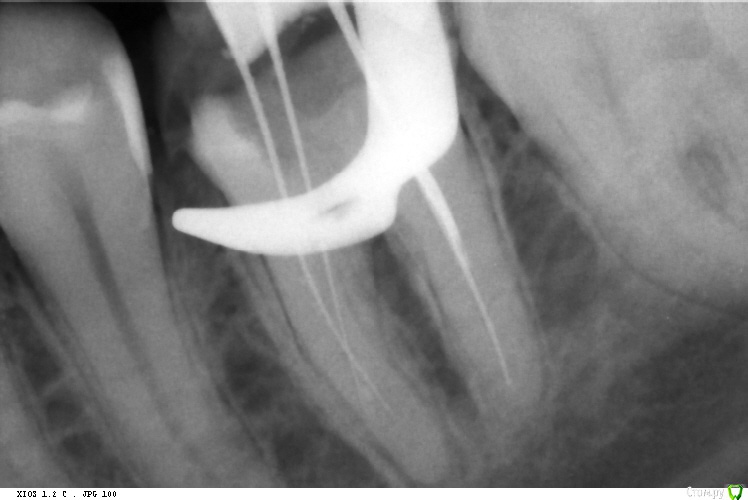

St. Опубликовано 26 декабря, 2015 Автор Поделиться Опубликовано 26 декабря, 2015 В продолжение темы из поста №17 http://forum.stom.ru/topic/29857-endo/?p=509407. Трещин не нашли, зато латеральку обнаружили В устье и апексе достаточно плотная РФП, в середине вообще было пусто. 6 Ссылка на комментарий

St. Опубликовано 22 декабря, 2015 Автор Поделиться Опубликовано 22 декабря, 2015 Немножко фейл... Надо таки было МТА закрывать, хотя и четкий апикальный упор был. 2 Ссылка на комментарий

DmitrySH Опубликовано 22 декабря, 2015 Поделиться Опубликовано 22 декабря, 2015 Анастасия, да протолкнули герметик, но ничего ужасного от этого не произойдет. Мне вот на финальном снимке интересно, это не трещина? Ссылка на комментарий

St. Опубликовано 22 декабря, 2015 Автор Поделиться Опубликовано 22 декабря, 2015 (изменено) Нет, это у нас со снимками беда.. По твердым тканям всё гуд. С силлером перебор случился. А пациентка вообще несчастливая. 47 уже удалили. Изменено 22 декабря, 2015 пользователем St. Ссылка на комментарий